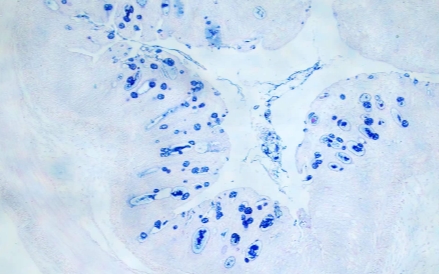

AB-PAS染色 是一种常用的组织化学染色方法,主要用于检测和区分组织中的酸性粘多糖和中性粘多糖。它在病理学、组织学和细胞学研究中广泛应用。

结果判读:

酸性粘液物质呈蓝色,糖原和中性粘液物质呈红色,混合型粘液物质呈蓝紫色或紫蓝色。